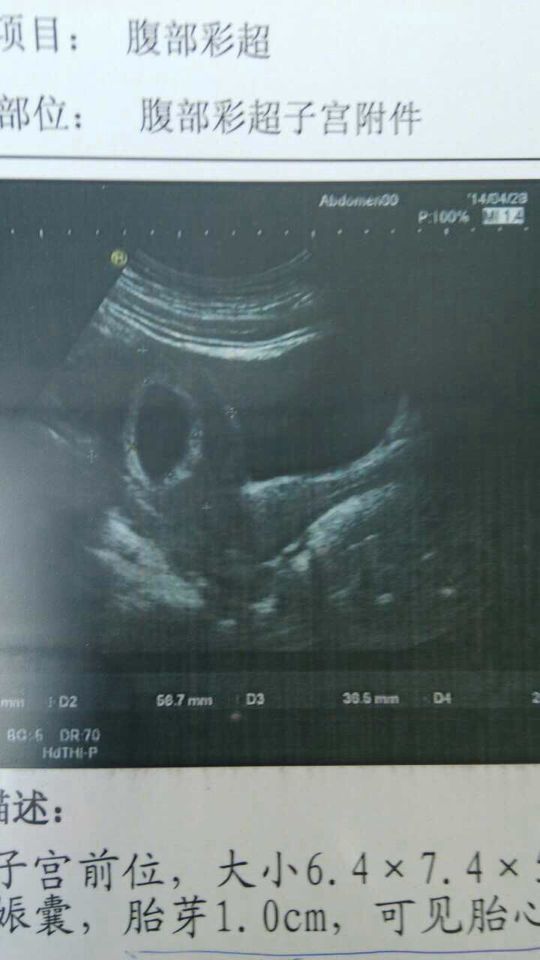

第一次的彩超结果是子宫前位,大小6.4*7.4*5.7厘米,回声均质,宫内见3.6*2.5cm大小

病情分析: 您的检查看胎儿的发育是正常的,按时产检就可以了 指导意见: 必要的情况下需要及时抽血化验HCG和孕酮检查,及时根据化验的情况看是否需要对症补充治疗